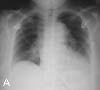

Severe chest pain in a hypertensive woman: The chest radiograph (A) shows a prominent mediastinum at the upper limits of normal. The aorta is ectatic, probably as a result of hypertension. The cardiac silhouette is within normal limits. Lungs are clear and unremarkable. You order a CT scan of the chest to investigate further.